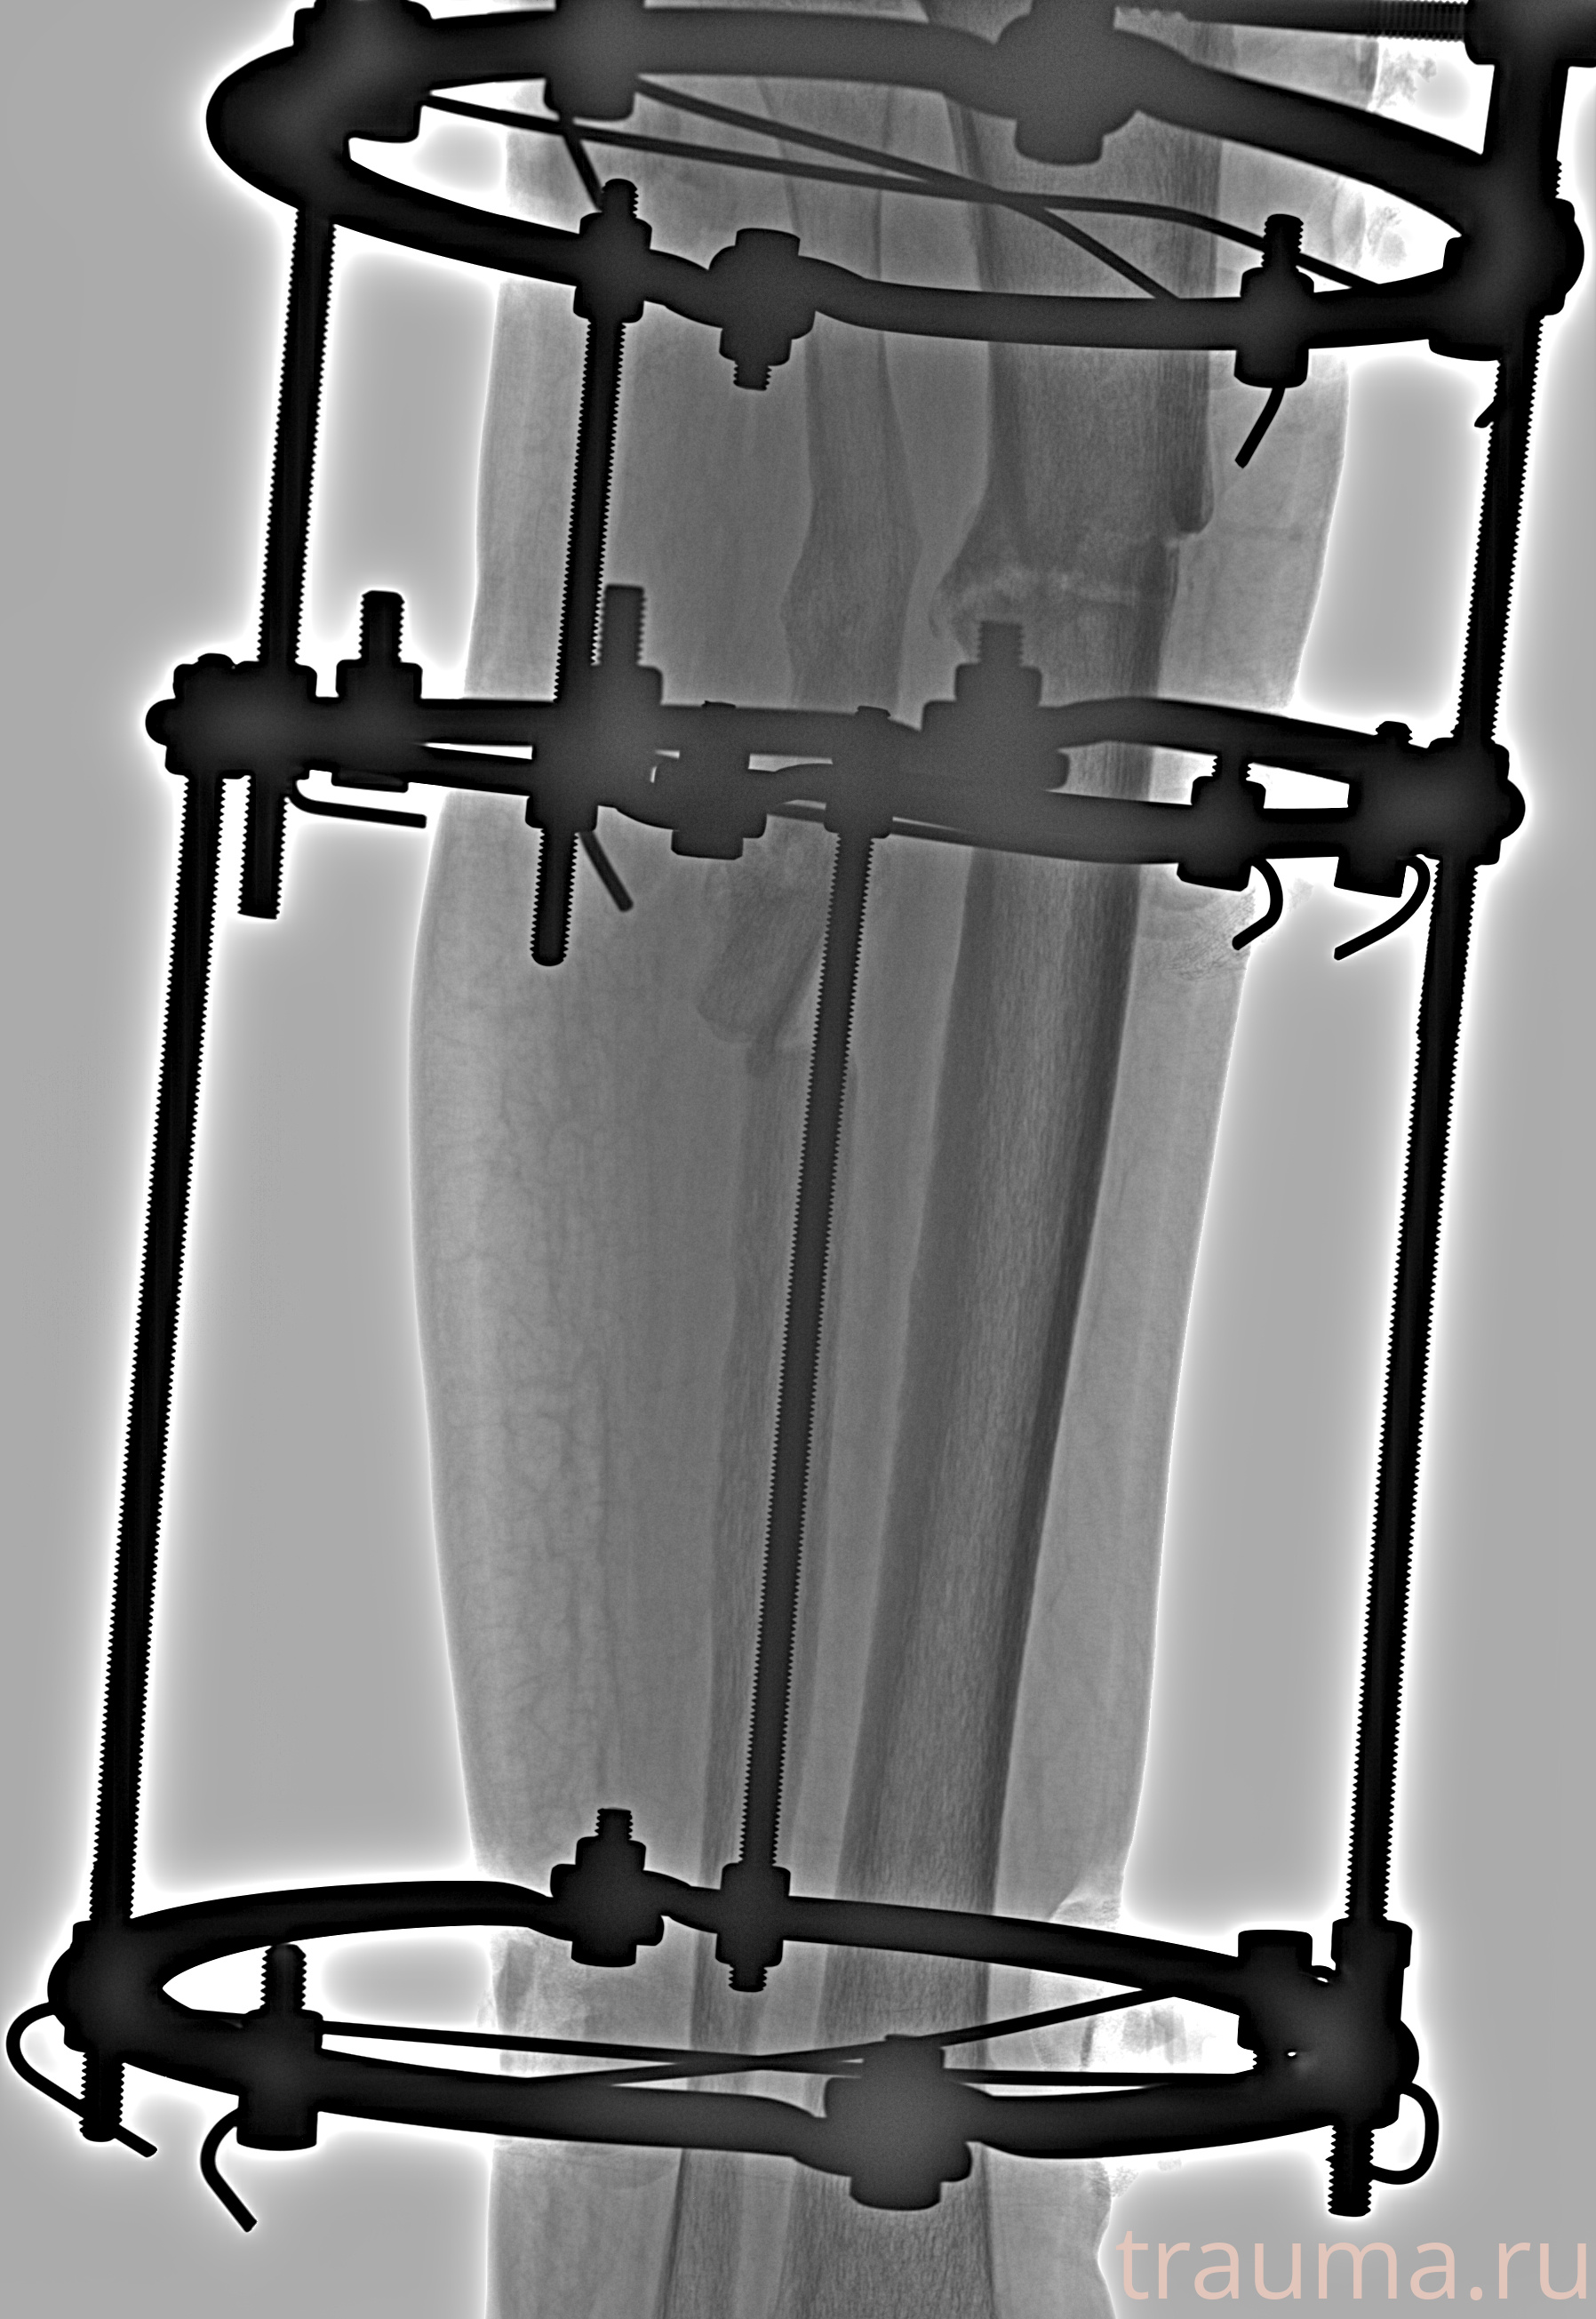

Рентгенограммы

Левая

Рентген на дому: по вашему адресу приезжает врач-рентгенолог, травматолог-ортопед с мобильным рентгеновским аппаратом, проводит диагностику травмы или заболевания, делает необходимые рентгенограммы, дает рекомендации по дальнейшему лечению. Получить качественные снимки в домашних условиях возможно благодаря уникальной методике, разработанной МосРентген Центром для института  Склифосовского